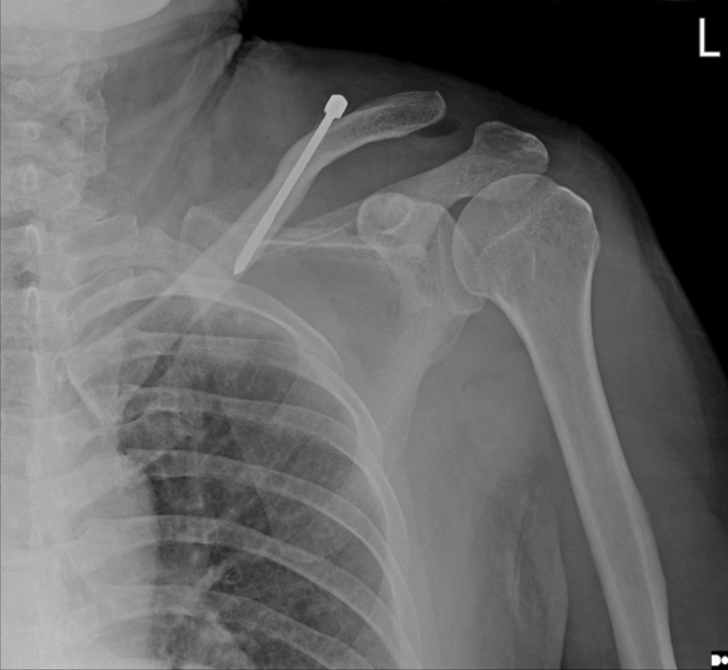

植入物取出后,胸片显示锁骨骨折完全愈合,随访1年,肩锁关节脱位保持良好复位